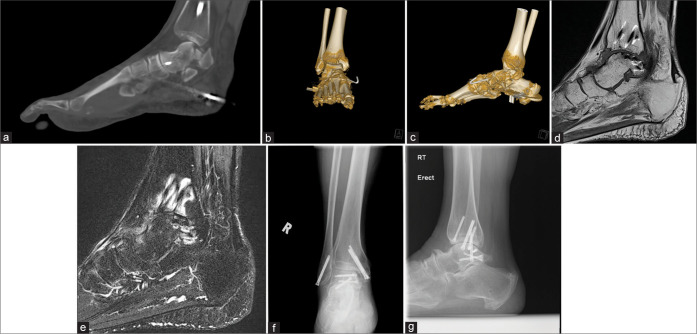

Objectives: The objectives of this study were to contribute to the limited existing knowledge about subtalar dislocations, analyze the computed tomography (CT) findings and advantages over radiography, and report the rate and potential risk factors of post-traumatic peri-talar osteoarthritis (OA).

Material and methods: A total of 23 cases of traumatic subtalar dislocation during a 15-year period at three regional hospitals were retrospectively reviewed.

Results: All 23 cases were closed dislocations. Successful close reduction was performed in 17 patients (73.9%) and 6 patients (26.1%) required open reduction and internal fixation. Twenty patients (87%) had associated foot and ankle fractures. Fractures of calcaneal medial tubercle were the most common (75%), followed by talar head (30%), sinus tarsi (25%), and medial malleolus (25%). The radiograph's sensitivity for identifying fractures was 48.1%. The mean follow-up period is 30 months. Symptomatic OA affected 8 patients (36.4%). No post-trauatic talar avascular necrosis was noted. Fractures were present in all of those patients with post-traumatic OA (100%). Three out of five patients who sustained high-energy mechanism injury developed radiographic OA (66.7%). Three out of six patients (50%) treated with open reduction and internal fixation also developed radiographic OA.

Conclusion: Subtalar dislocation remains a rare injury. It is strongly associated with foot and ankle fractures. Fractures of the calcaneal medial tubercle were the most common. The risk of post-traumatic symptomatic peritalar OA is high. CT is useful in detecting occult fractures and injured bony subregions. We postulated potential risk factors of post-traumatic OA (fracture, high-energy mechanism of injury, open reduction, and internal fixation); however, this requires further study.